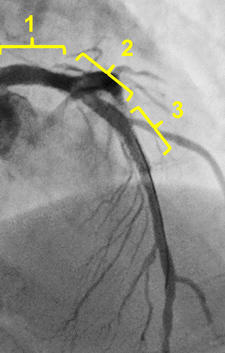

ST-01 mother-and-child catheter inserted and the rota burr removed successfully

Blood pressure was correct. Non compliant balloon inflation, no extravasation.

One stent strategy

Final angiography

The final IVUS showed stent was apposed correctly and fully expanded.